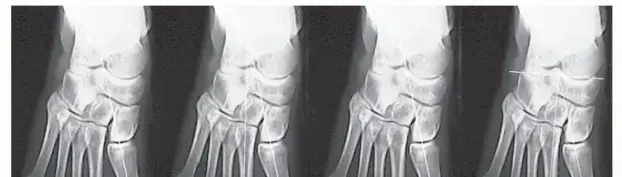

ماذا يحدث في حالة إبهام القدم الأروح؟

في حالة إبهام القدم الأروح، ينحرف إصبع القدم الكبير باتجاه الأصابع الأخرى، بينما تتحرك العظمة المشطية الأولى (التي يتصل بها إصبع القدم الكبير) باتجاه الداخل. هذا الانحراف يبرز رأس العظمة المشطية الأولى إلى الخارج، مكوناً النتوء العظمي المؤلم الذي نسميه "الوكعة". هذا التغير في المحاذاة يخل بالتوازن الدقيق للمفصل، ويؤثر على عمل الأوتار والسمسمانية، مما يؤدي إلى الألم والالتهاب وصعوبة الحركة.